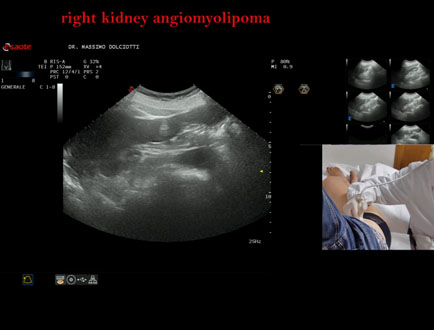

Motivazione dell'esame: follow up x angiomiolipoma renale destro.

Commento all'esame: le immagini ed il video documentano il rene destro ptosico, di ecostruttura disomogenea per evidenza in sede corticale polo inferiore di immagine iperecogena, delle dimensioni di 26 x 19 mm, da ricondurre, come prima ipotesi, ad angiomiolipoma. Il rene sinistro è ptosico, di ecostruttura disomogenea per evidenza in sede mesorenale corticale di immagine iperecogena, delle dimensioni di 10 mm, da ricondurre, come prima ipotesi, ad angiomiolipoma.

Conclusioni: grande angiomiolipoma al rene destro e piccolo angiomiolipoma al rene sinistro (large angiomyolipoma in the right kidney and small angiomyolipoma in the left kidney).